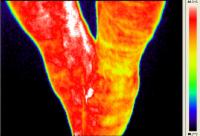

Temperaturwert = Farbwert | temperature value = colour value |

Rasmus - Pferd mit Arthrose - Horse with Osteoarthritis